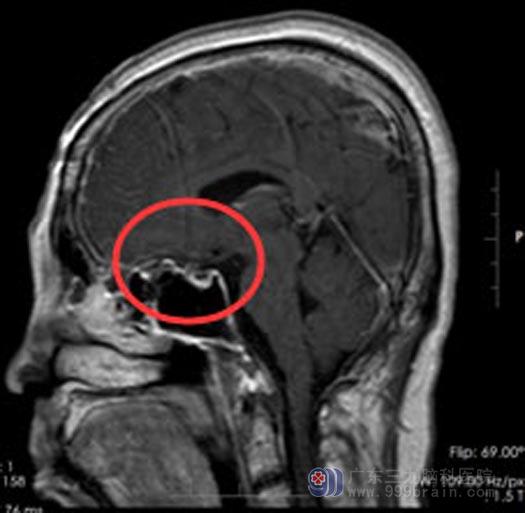

入住广东三九脑科医院综合神经外科后,立即紧锣密鼓地准备手术,这是和时间在赛跑,因为只要双眼视力完全丧失,那就再无回天之力。由鲁明主任主刀行“鞍结节脑膜瘤切除术”,术中见肿瘤已经将左侧视神经压扁,庆幸的是,手术很顺利,肿瘤完全切除,双侧视神经得到了充分的减压。术后,陈阿姨的视力有了明显改善,头痛头晕症状也得到缓解。

手术后